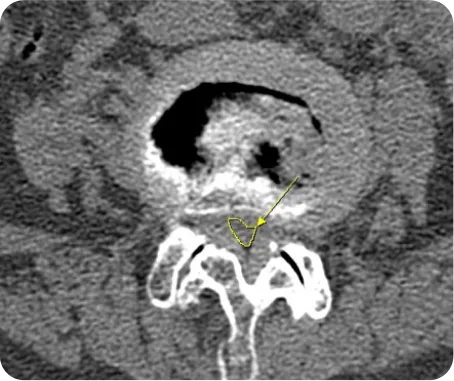

▲ 척추관협착증 환자의 CT

CT *

1. 골절 및 변형의 정확한 양상을 입체적으로 파악

2. 골절 이후 뼈의 유합된 정도를 판단

3. 뼈의 여러 방향에서 절단면을 얻을 수 있어서 미세 골절 및 뼈가 겹쳐있는 부위의 골절을 진단

4. 디스크나 협착증 환자의 경우 사고로 인해 악화된 경우 CT로 확인

5. 사고의 충격으로 인한 뇌진탕 여부를 확인